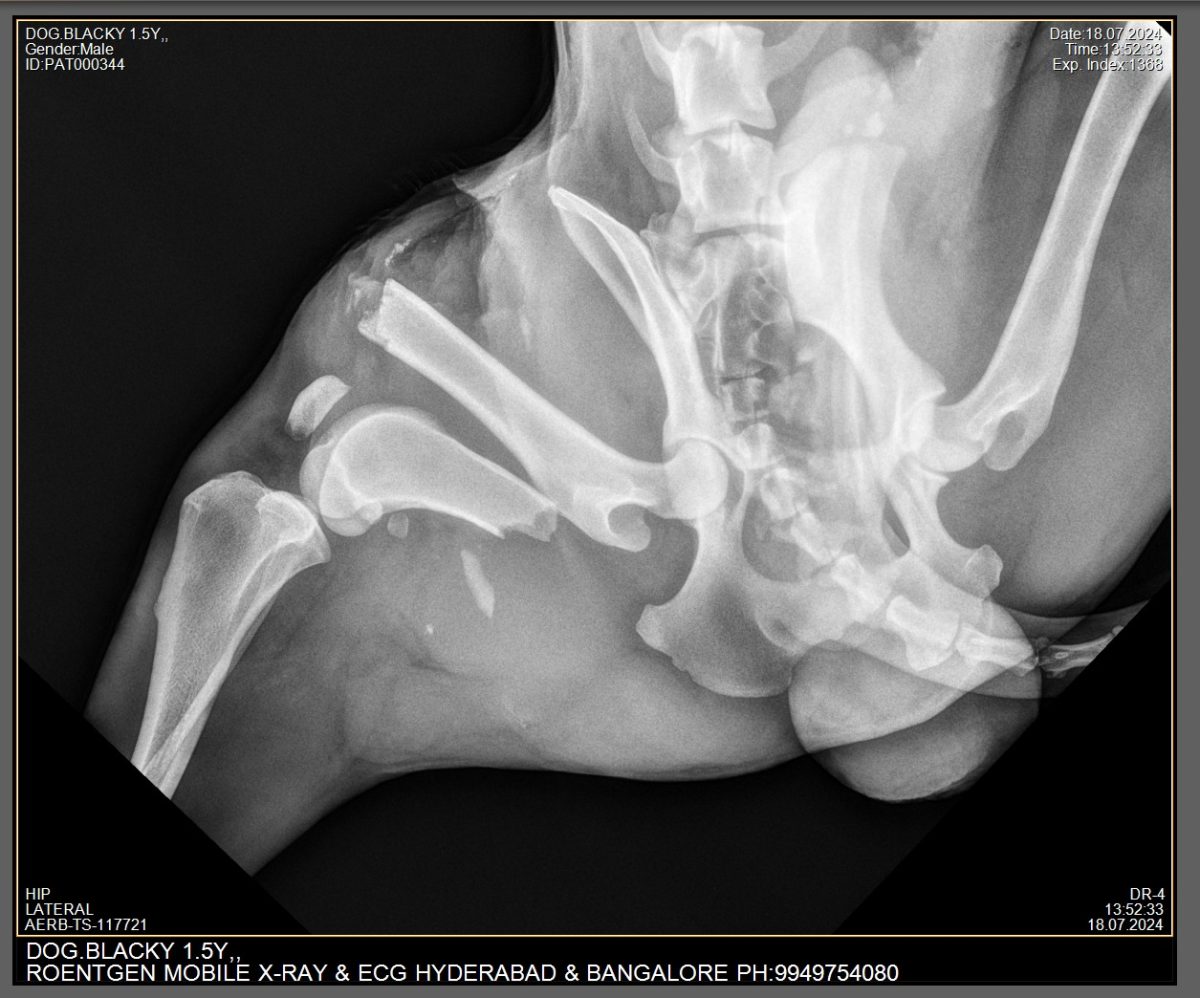

X-RAY FOR PETS

We will do X-Ray for pets at home